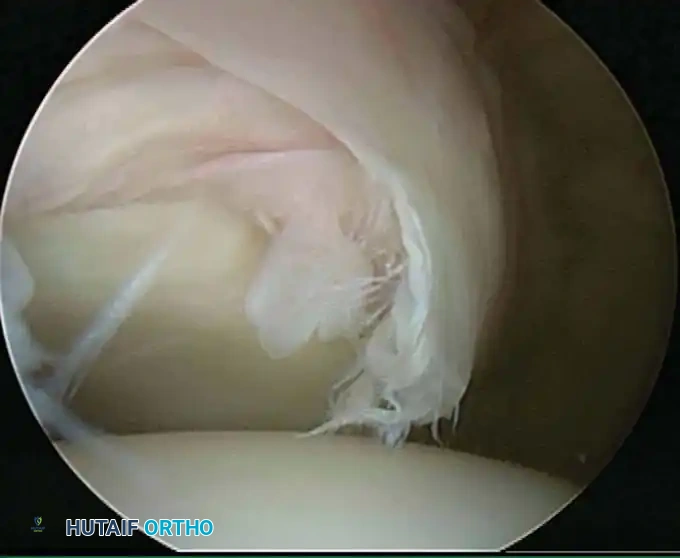

Once diagnostic evaluation is complete and hemostasis is secured, the therapeutic phase commences. Whether performing a SLAP repair, a Bankart stabilization, or a rotator cuff repair, the principles of tissue mobilization, anatomical footprint restoration, and secure biomechanical fixation remain paramount.

Modern arthroscopy relies heavily on suture anchors (biocomposite or all-suture constructs) and advanced arthroscopic knot-tying or knotless techniques. The ability to pass sutures through retracted, fibrotic tissue and secure them under appropriate tension without strangulating the microvascular supply is the hallmark of a master arthroscopist.